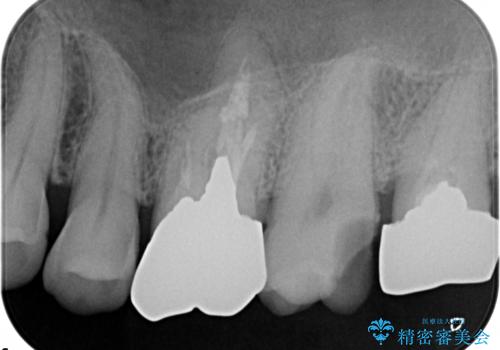

ゴールドインレーによる修復治療

- 他院で入れた銀の詰め物が取れたことを主訴に来院されました。

内部の虫歯を除去し、ゴールドインレーにて修復治療を行っております。

ゴールドインレーは適合が良く、割れることもないため、長期的に安定した治療法となります。